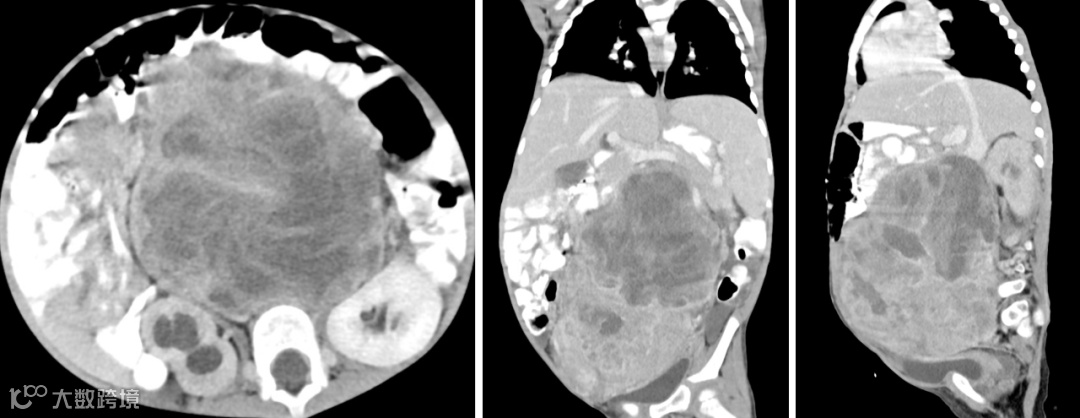

CT

平扫表现为等或低密度肿块

增强扫描强化不均匀。

患者,女,3岁,腹膜后RMS。肿块从上腹部延伸至盆腔右侧,并充满大部分腹腔,平扫呈等低混杂密度,其内可见液化坏死区,增强扫描不均匀强化。膀胱受压向左移位,腹主动脉和髂血管移位并被肿块左侧包裹。